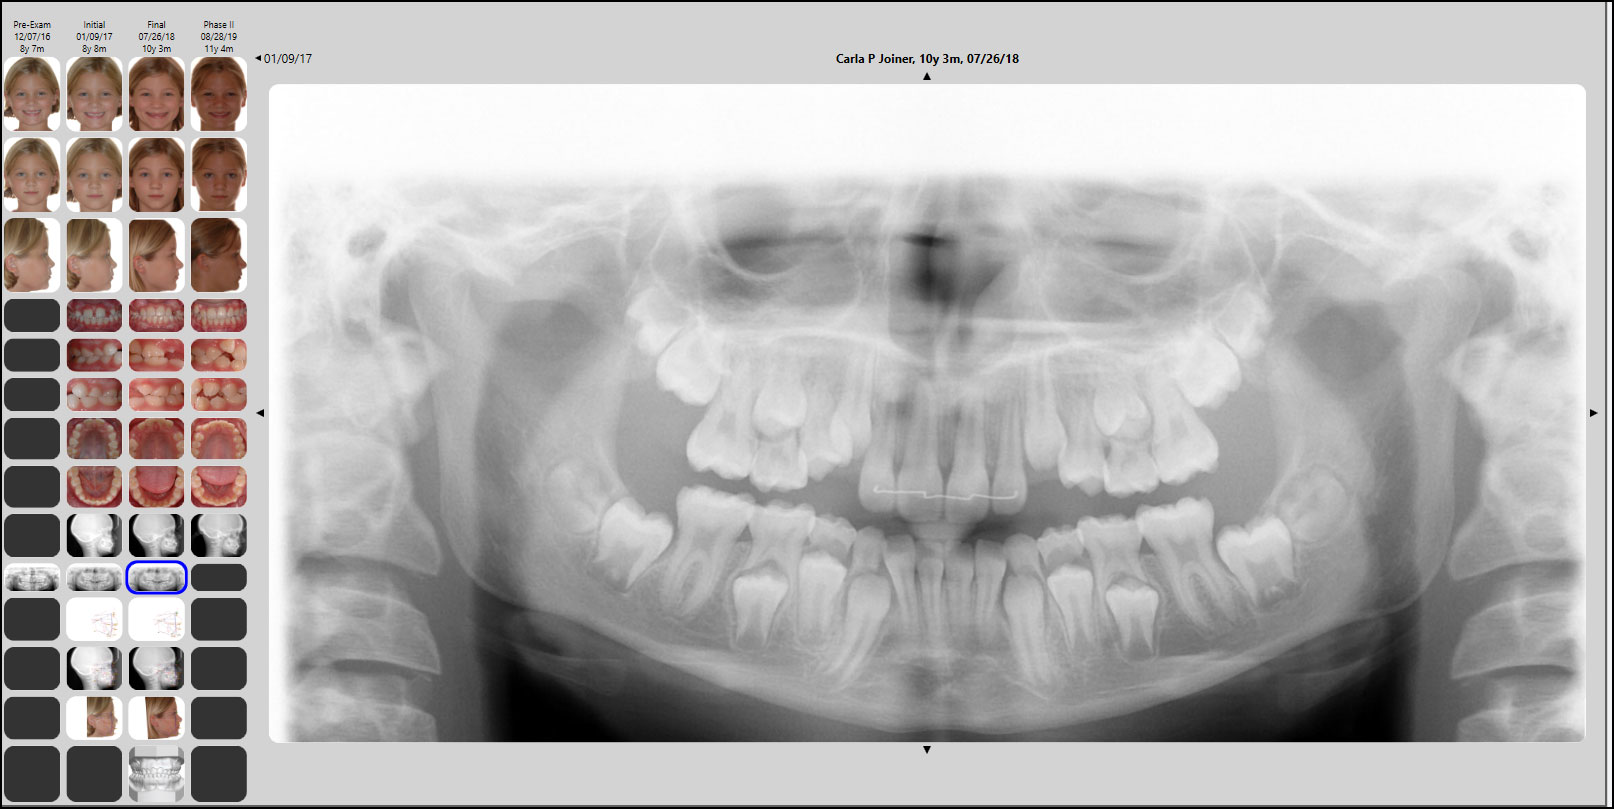

Ceph Tracing and Analysis

Ceph tracing makes your life simpler by automatically selecting and positioning each structure to be traced, then prompting you for final placement. With SmartCeph, you can superimpose multiple timepoints by plane or manually align them on the fly to meet your specific needs.